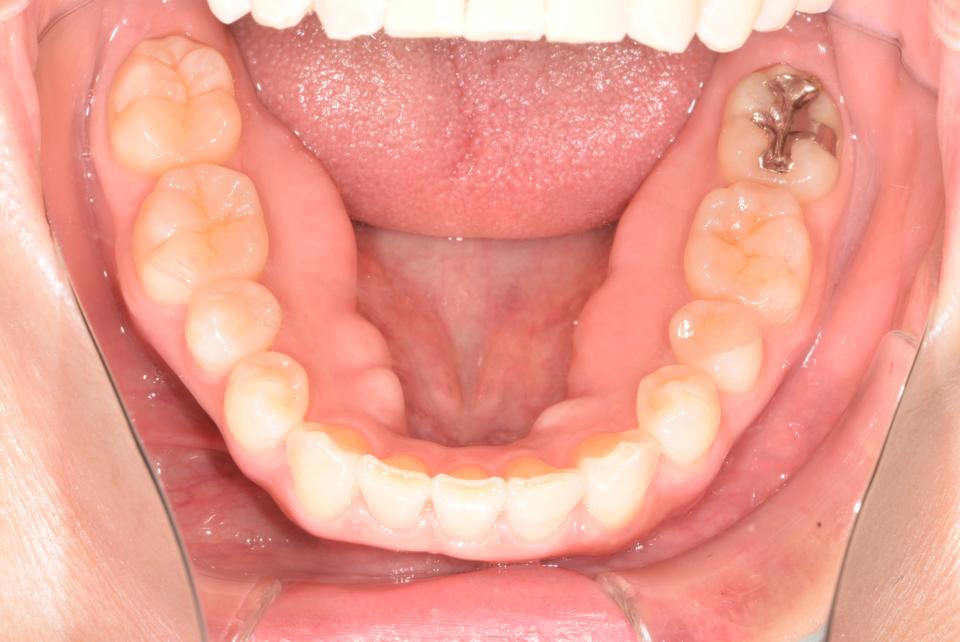

八重歯のマウスピース型矯正治療例(抜歯あり)

矯正治療後

上の左右4番目の抜歯をして、マウスピース型の矯正治療装置を使用し、歯のやすり掛け(IPR)を行いました。

現在はマウスピース型のリテーナーでで後戻りの防止をして定期的にチェックをしています。

| 年齢・性別 | 40代女性 |

| 矯正治療期間 | 1年10か月 |

| 抜歯の有無 | 上左右4番抜歯 |

| 治療費 |

880000円(検査料、装置料、施術料) |

| リスク・注意点 |

歯の移動に伴い痛みを感じる場合がある 治療後保定装置を使わないと後戻りを生じる |